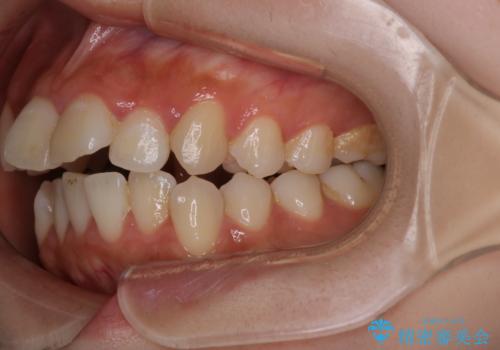

【インビザライン】マウスピースで開咬改善

- 開咬を主訴に来院されました。

IPR(歯と歯の間を削る処置)と顎間ゴムを行いながら、インビザラインで開咬を治療する計画を立てました。

治療をしながら、MFT(口腔筋機能療法)も行っていくことにしました。

歯の移動量が多いケースでしたが、患者様にマウスピースの使用とゴム掛けを頑張っていただいたので

リファイメント1回のみで治療を終わることができました。